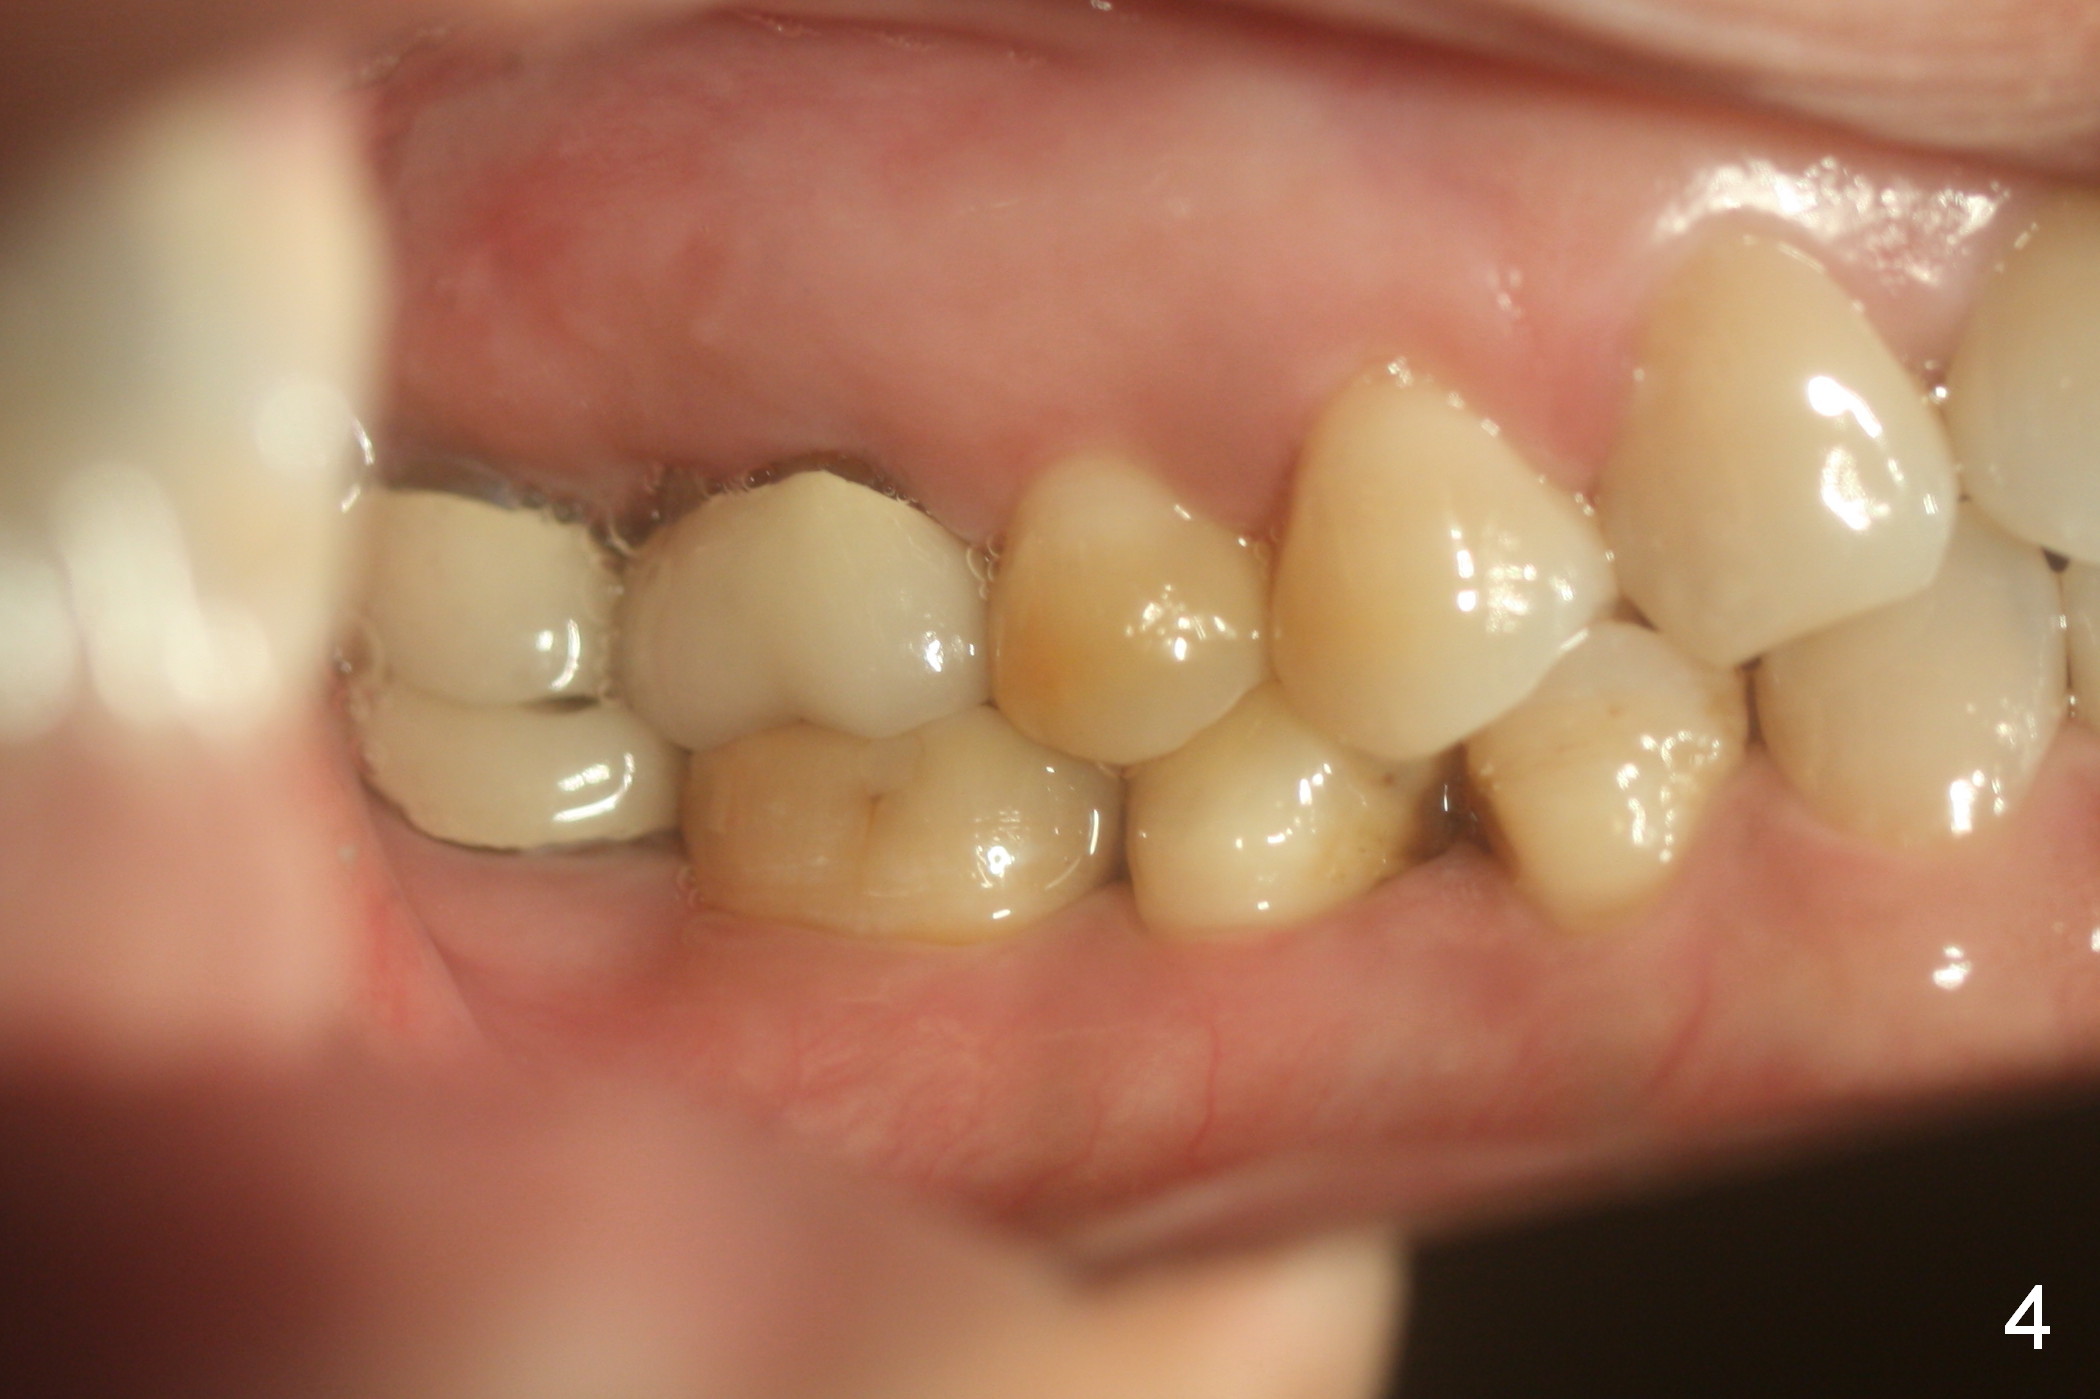

Show the patient that the tooth #31 is severely mesially tilted with reduction in the mesiodistal width for implant placement (Fig.5,7). The tooth #32 is severely malpositioned (linguoversion, Fig.6). It is extremely difficult to gain space for the implant without #32 extraction.